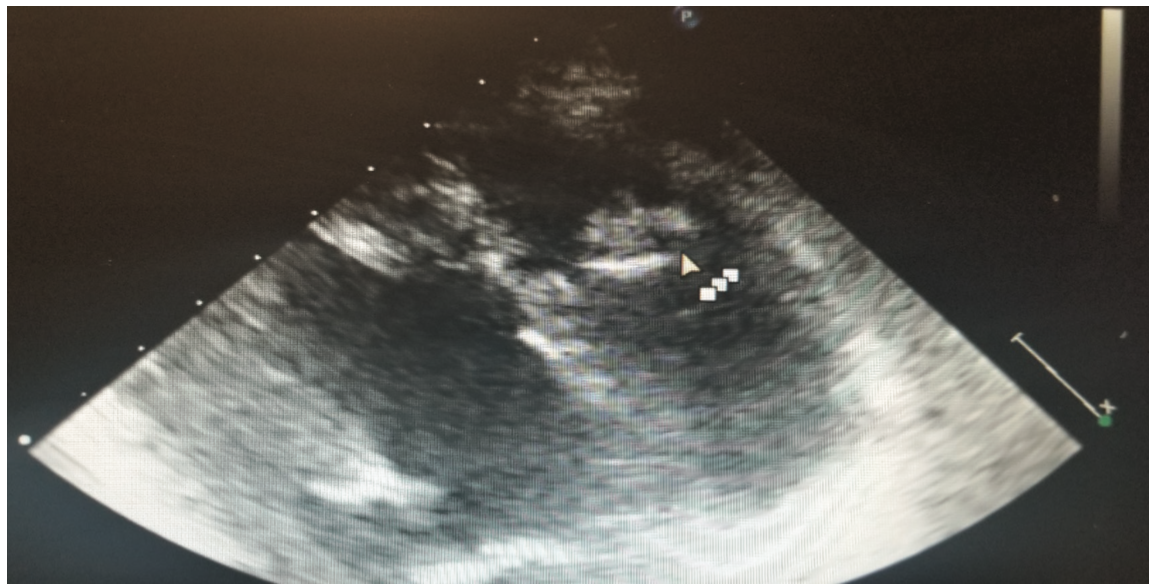

This is a 58-year-old female with a history of tuberous sclerosis. Transthoracic echocardiogram images demonstrated a heterogeneous mass in the mid right ventricle attached to the septum and the moderator band (Figures 1-6). The mass looked similar to what was seen on a transthoracic echocardiogram from a year prior.

One of the major differentials for this mass was thought to be cardiac rhabdomyoma, given the patient’s history of tuberous sclerosis with known renal angiomyolipomas. Cardiac rhabdomyomas are usually associated with tuberous sclerosis complex, which is a genetic disorder characterized by hamartomas in multiple organs. Rhabdomyomas may develop at any location in the heart, but the most common locations are ventricular and septal walls.